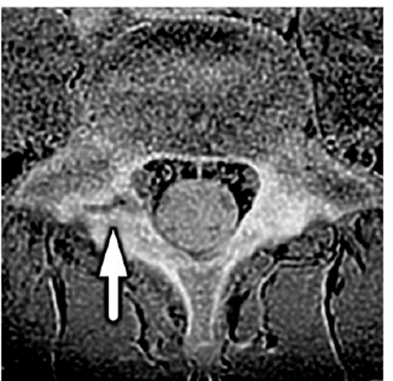

図2: 腰椎分離症のMR画像(画像は腰椎の水平断面を示す。矢印は腰椎分離症の病態箇所である)

その結果、片側腰椎分離症の選手では、分離症側の大腰筋が対照群より小さく(約12%)、左右差が認められました。一方で、多裂筋と脊柱起立筋には明確な差がみられませんでした。さらに、ASLRで「腰椎分離症側の骨盤が沈む」現象は腰椎分離症を有する選手に多く、ASLRが陽性だった16名のうち13名が片側腰椎分離症を有していました。これらは、片側腰椎分離症では「深部筋(大腰筋)の左右差」と「脚上げ動作での骨盤の安定性低下」がみられる可能性を示します。